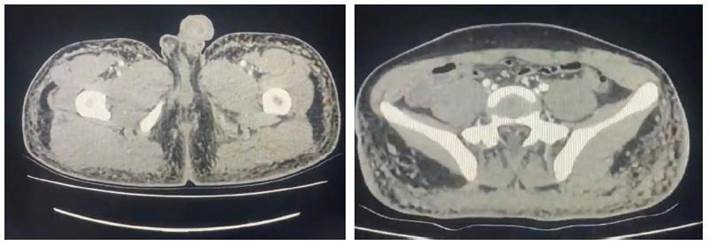

Los exámenes auxiliares proporcionan hemograma con leucocitos: 10 650/mm3, plaquetas: 321 000/mm3, hemoglobina: 6,9 g/dl, volumen corpuscular medio: 87,4 fL, hemoglobina corpuscular media: 29,9 pg. Los exámenes bioquímicos, bilirrubina total: 0,40 mg/dl, bilirrubina directa: 0,10 mg/dl, creatinina: 0,58 mg/dl, urea: 40 mg/dl, deshidrogenasa láctica: 233 UI/L, proteína C reactiva: 2,7, ferritina: 116 mg/dl, dímero D: 1,02 µg/ml, ELISA-VIH I-II: no reactivo, prueba ARN para SARS-CoV-2 en muestra respiratoria por RT-PCR en tiempo real: negativo, prueba rápida antigénica COVID-19: no reactiva, baciloscopia directa para Mycobacterium tuberculosis en orina, heces y esputo: negativos. Radiografía de tórax posteroanterior: patrón alveolointersticial periférico a predominio bibasal; radiografía de tórax (Figura 1), tomografía espiral multicorte con contraste de tórax: áreas de vidrio delustrado periférico respetando área central (Figura 2); tomografía espiral multicorte con contraste de región glútea (Figura 3): nódulos granulomatosos a cuerpo extraño asociados a signos inflamatorios en plano graso subcutáneo de la región glútea y muslos proximales derecho e izquierdo. Recibió oxacilina y clindamicina endovenosas por sospecha de infección de partes blandas en lugar de inyección, anticoagulación terapéutica por sospecha de tromboembolismo, corticoterapia durante 9 días y soporte oxigenatorio. La evolución fue favorable, por lo que fue dado de alta después de 10 días.

De acuerdo con la literatura, las edades de los casos varían entre los 20 a 55 años, y se presentan con mayor frecuencia en el sexo femenino; en menor cuantía, en los varones transexuales. Respecto a la clínica de presentación, va desde dificultad respiratoria, dolor torácico de tipo punzante u opresivo, fiebre, tos seca (1,5,7-10,11,12,13 y hemoptisis 14; así mismo, la presentación puede ser aguda, dentro de las primeras 24 horas tras la inyección, y latente, en donde se reportan casos de hasta 13 meses. La cantidad de geles de silicona inyectada repercute en el inicio de los síntomas, y se describe que desde 100 ml de inóculo a más puede presentarse en forma aguda 4. Al ingreso, se han reportado distintos grados de hipoxemia en los análisis de gases arteriales 1,4,7,15. Las imágenes encontradas en las radiografías de tórax al ingreso van desde una radiografía normal 2, un patrón alveolar difuso 13,15, reticular difuso bilateral 4,8,9, alveolar difuso bibasal y periférico 1,3, este último presente en nuestro caso; las tomografías de tórax computarizadas, de acuerdo con los informes, mostraron al ingreso áreas de consolidación a predominio bibasal 9,15, en parches y áreas en vidrio deslustrado periférico 3,4,8,13, algunos con broncograma aéreo (1y) de nódulos pulmonares no clasificados; la predominancia del compromiso periférico en vidrio deslustrado respetando el área central presente en nuestro caso, que según Soeroso cataloga como muy "sugerente de inyección de silicona líquida". Asimismo, se planteó la sospecha de tromboembolismo pulmonar; sin embargo, fue descartado dada la probabilidad clínica baja luego de aplicar la regla de predicción clínica de Geneva y el score de Wells, por lo que no se justificó realizar otro examen diagnóstico más específico.